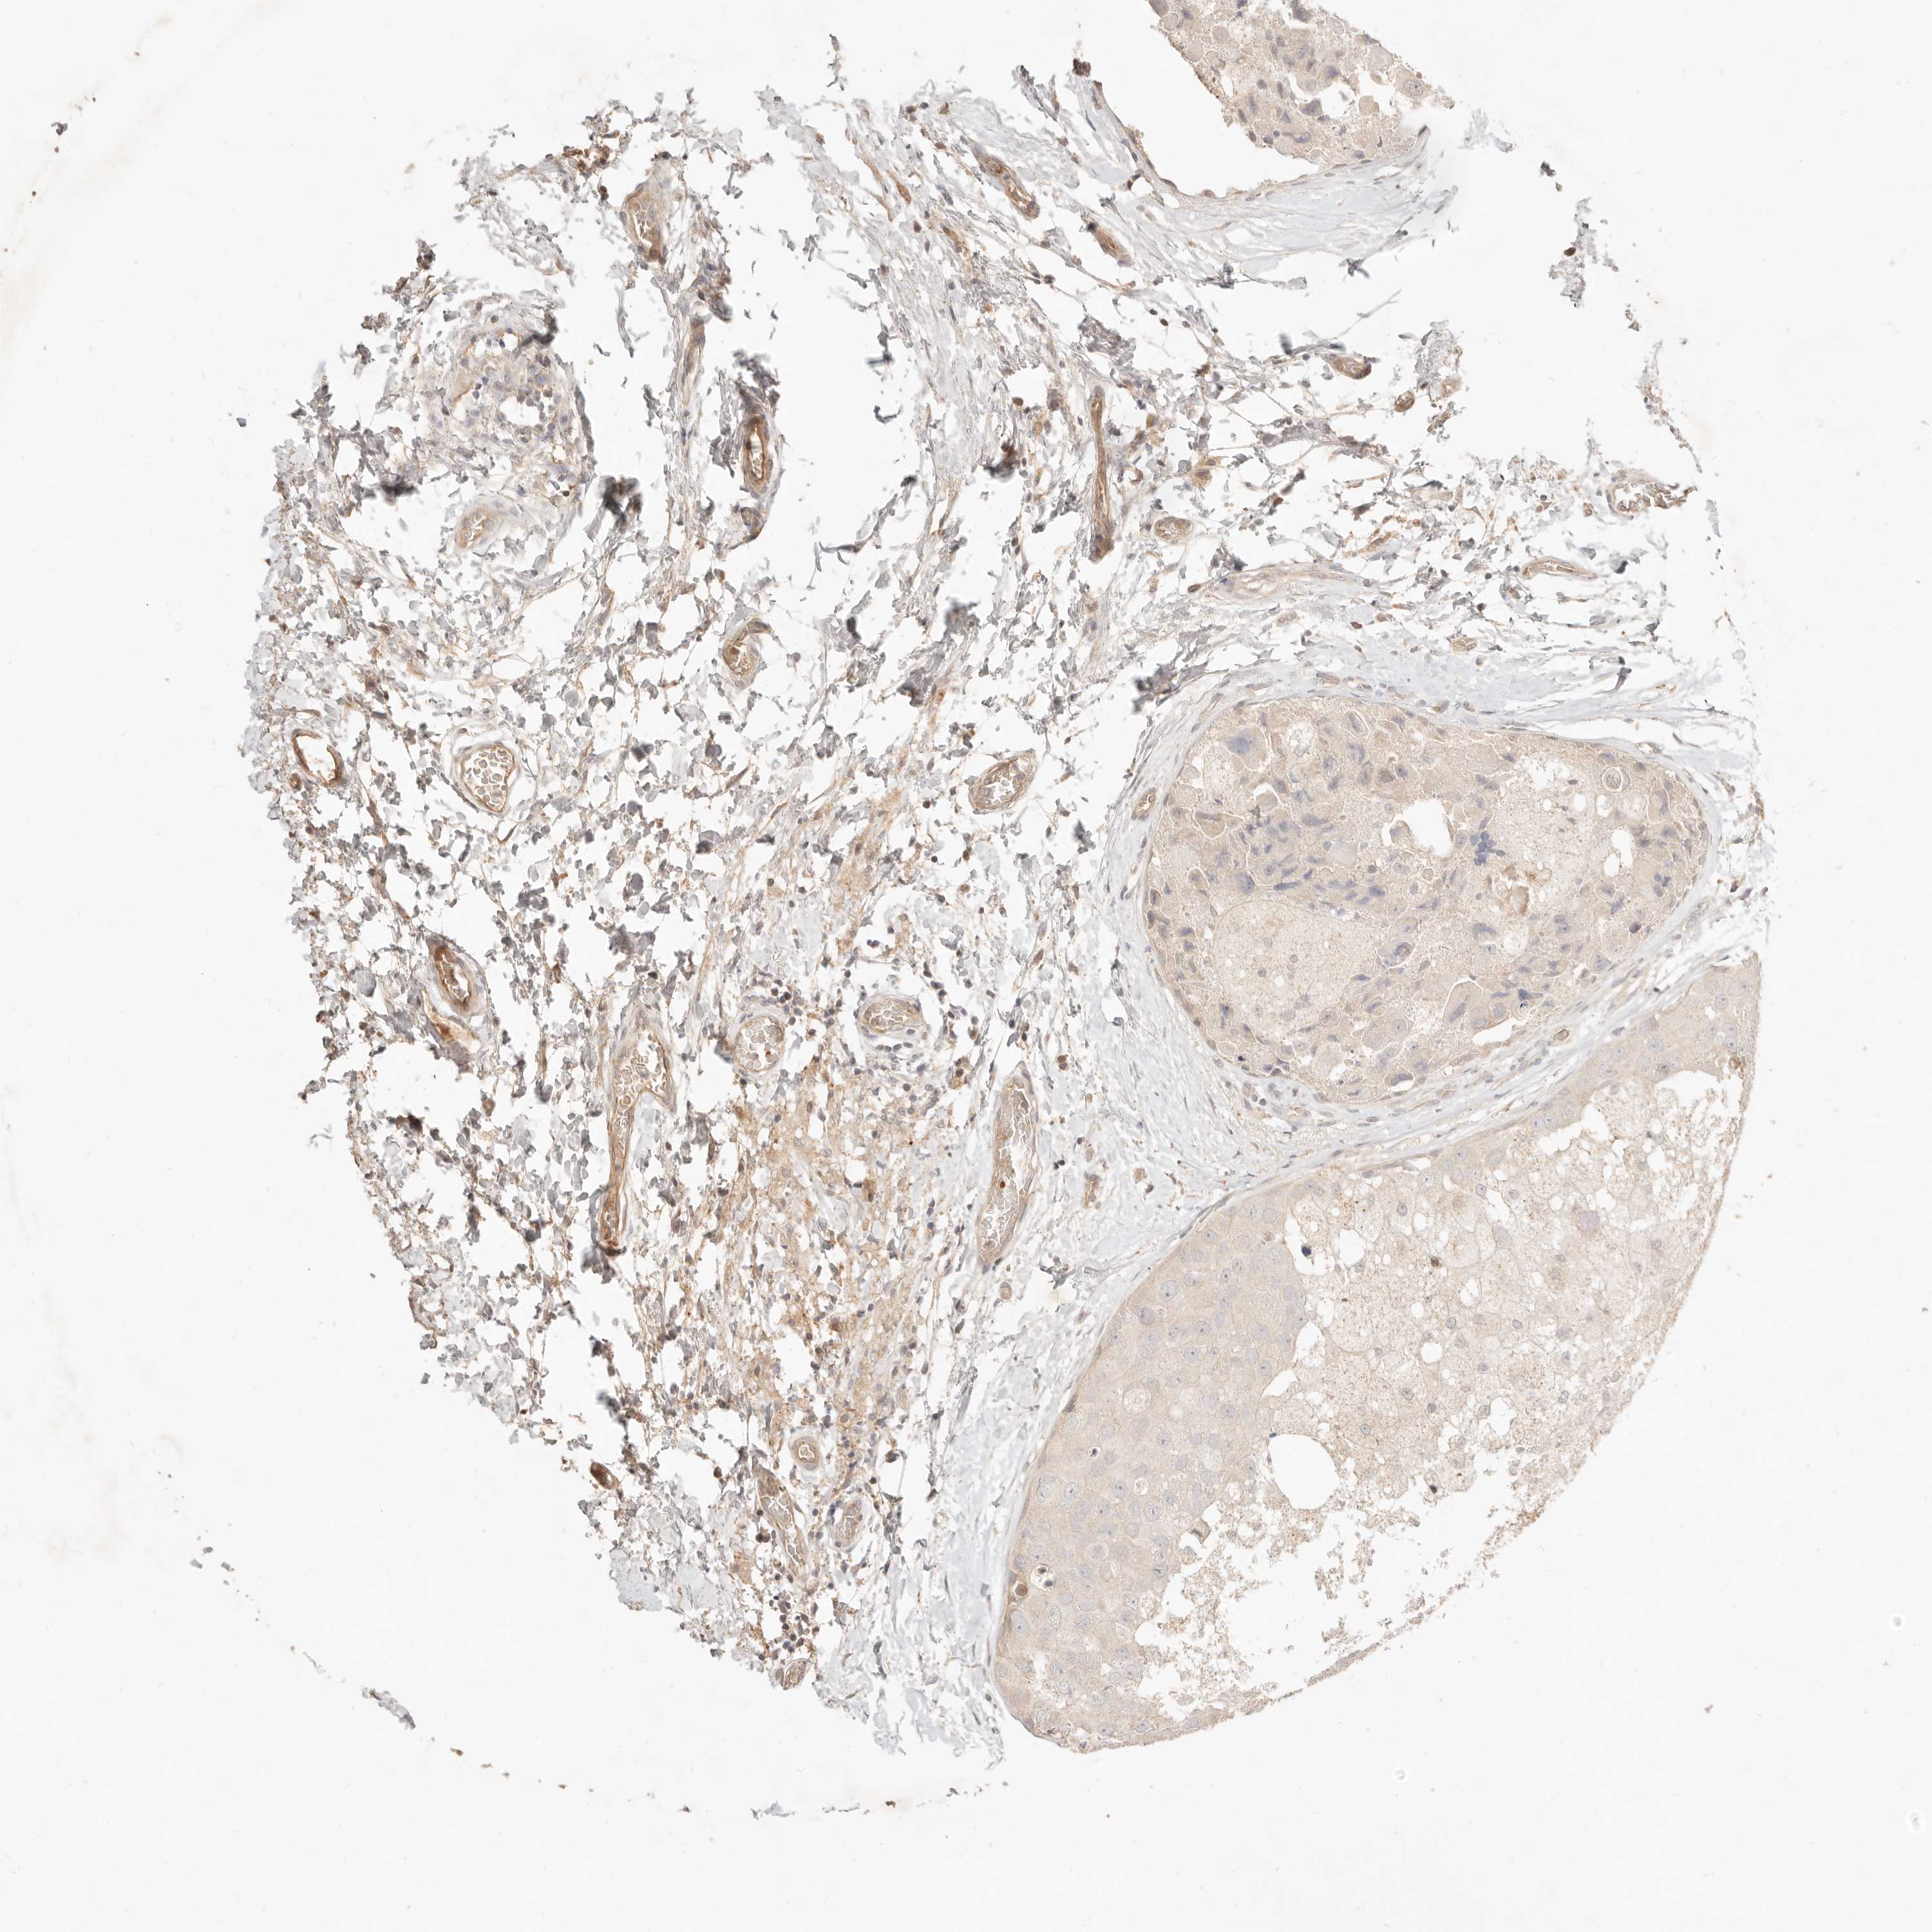

BRCA TCGA BRCA VALIDATION PROTEIN EXPRESSION